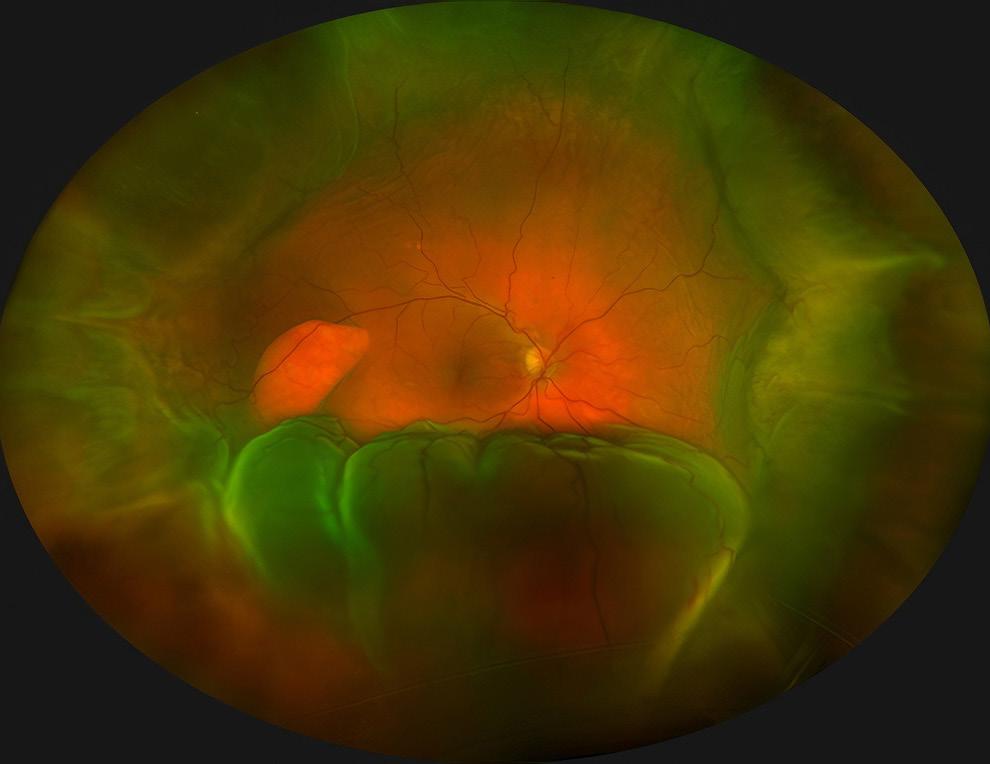

OPS Exhibit at AAO, First Place in the Video Category: Giant Cell Arteritis, Second Place in the Fluorescein Angiography Category: Unknown Third Place in the Fluorescein Angiography Category: Sickle Cell Retinopathy, Honorable Mention in Gonio Photography: Unknown, Honorable Mention in Ultra-Widefield Imaging: Choroidal Detachment with Retinal Tear.

Select Photography Award Images, clockwise from top left: Posterior Uveitis by Christopher Keth, BA, CRA; Santos Klimt by Veronica Jones, BA; Sickle Cell Retinopathy by Christiaan Lopez-Miro; Choroidal Detachment with Retinal Tear by Christiaan Lopez-Miro.